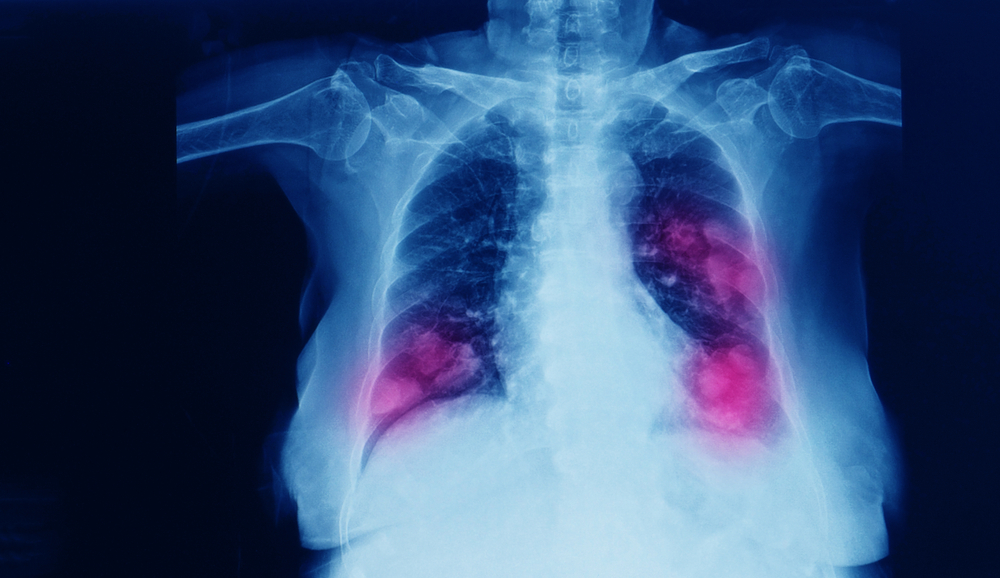

Lung cancer is a complex disease with a variety of causes. There are different types of lung cancer tumors, as well as an array of symptoms. An accurate diagnosis is crucial for the best prognosis possible. Once a doctor suspects lung cancer, he or she may order imaging such as a CT scan, MRI, or PET scan. If these tests indicate lung cancer, a biopsy including Guardant 360 testing, ultrasound, mediastinoscopy, thoracoscopy, or wedge resection may be the next step. Once the doctor has staged the tumor, they have a better idea of how fast it will grow, how large the tumor is, and whether it has progressed beyond the initial site. Cancer treatments are changing rapidly, with new innovations and new treatments that can save lives.